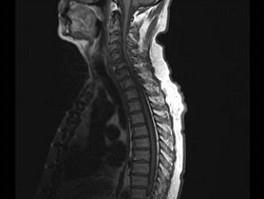

问题 男,65岁,颈部疼痛,双下肢无力3月余,请结合影像学检查,选出最可能的诊断 ( )

选项 A、小关节面综合征 B、椎管狭窄 C、脊膜瘤 D、脊膜膨出 E、脊髓空洞症

答案 B